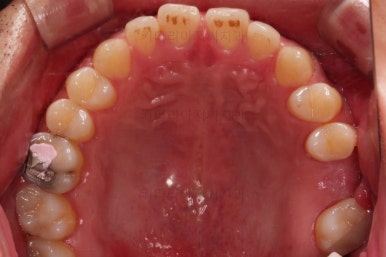

초진 시의 입안 모습입니다.

어금니가 빠져서 결손치아가 있고 치아 사이에 틈새도 있어서 교정치료도 함께 원한다고 내원해 주셨어요.

사진에서 보시는 바와 같이 윗니 1개, 아랫니 1개의 결손 부위가 보입니다.

윗니 어금니 중에는 신경치료를 마무리 못하고 임시재료로 메꿔뒀던 부위도 보이고요.

충치치료가 완료된 부위는 골드 크라운(금니)이 씌워졌어요.